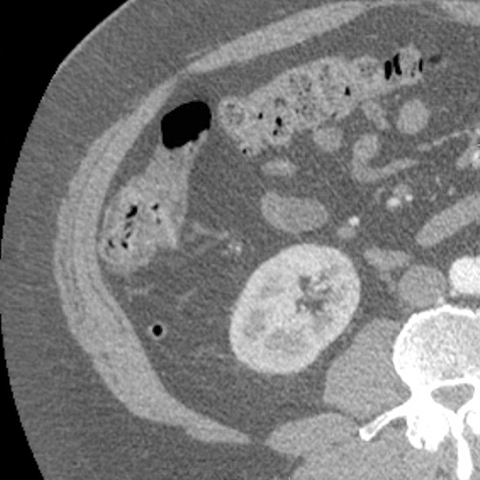

Appendix behind Ascending Colon, CT (axial) [6 of 6]